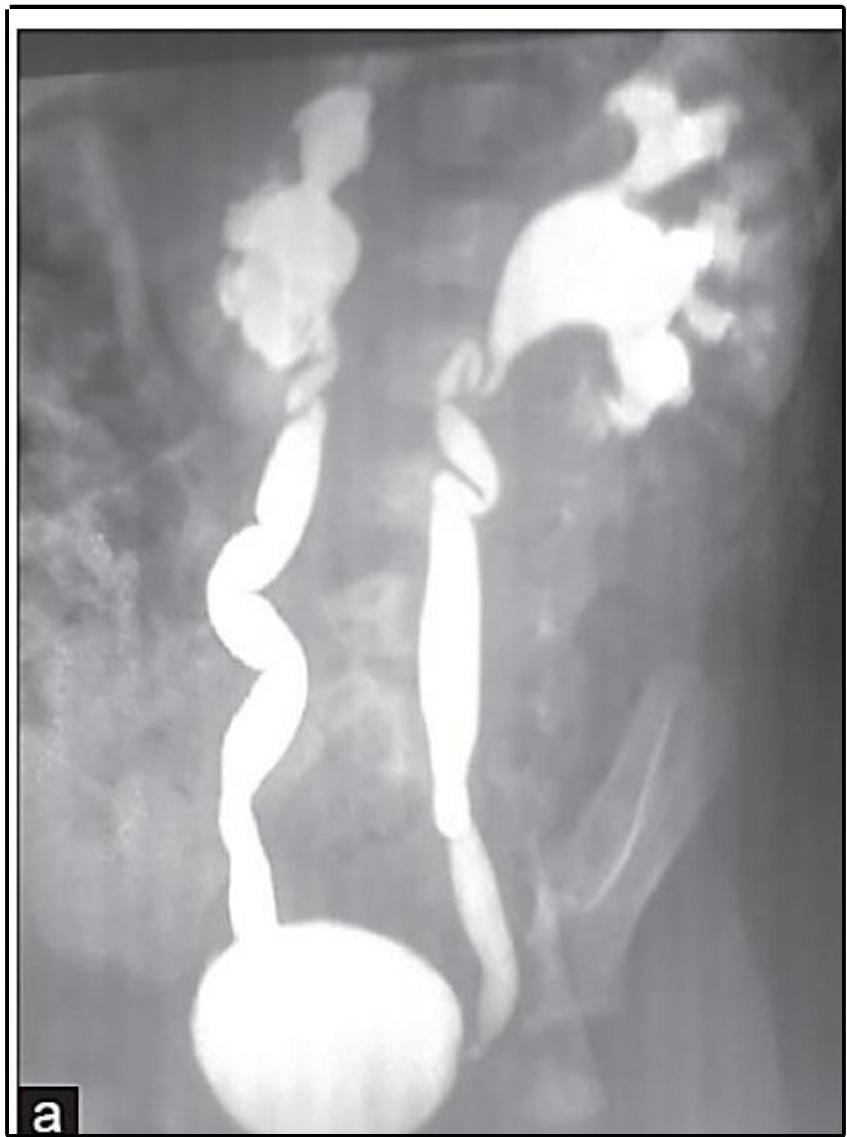

Vesicoureteral Reflux (VUR) — MCUG/VCUG

Scenario: Infant referred for evaluation following recurrent UTI.

Investigation? Micturating cystourethrogram (MCUG) / Voiding cystourethrogram (VCUG)

Findings?

- Posterior urethral valve

- Dilated ureters and bladder

- Tortuous ureters

- Dilated renal pelvis and calyces bilaterally (hydronephrosis)

Diagnosis? Vesicoureteral Reflux (VUR) — grade 4-5.

Diagnosis & Grading

- Studies: Renal US (Typically first); MCUG (to confirm diagnosis); RNC (for follow-up).

International Grading System (MCUG Findings):

| Grade | Description / Findings |

|---|---|

| Grade I | Into a nondilated ureter only. |

| Grade II | Into the pelvis and calyces without dilation. |

| Grade III | Mild to moderate dilation of ureter, pelvis, and calyces; minimal blunting of fornices (become close). |

| Grade IV | Moderate ureteral tortuosity and dilation of pelvis and calyces (adhered to each other). |

| Grade V | Gross dilation; significant tortuosity; loss of papillary impressions; blunting of calyces (bilateral/severe). |